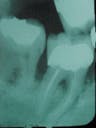

In 1989, I made the decision to stay at home with my children, so I lost contact with Mr. Davis. However at his recare visit in 1991, slight evidence of graft deterioration is visible. In the interim period between 1989 and 1991, he had undergone endodontics and had a PFM crown placed on the tooth.

At this visit in 1993, further evidence of graft breakdown is evident.

1991

1993